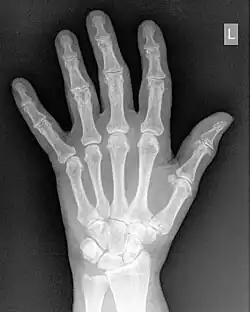

- Contrast enhancement can also be effected through manipulation of the image's statistical histogram and is illustrated in Figure 5.8. A histogram is a plot of the frequency of occurrence of each pixel value in an image - see panel (a) for an example, where this frequency is plotted as a function of pixel value. It can be seen that pixels from the black surroundings of the hand are indicated by the peak at low pixel values. It can also be seen that the pixel values representing bone and tissue attenuation form a broad range of lower frequencies extending to just over half the grey scale. Indeed the pixels of the 'L' marker can be seen to form an isolated blip at a pixel value of 75. Note that the term frequency as used here should not be confused with the term spatial frequency we have been using in our discussion of Fourier techniques.

- Manipulating such histogram data can be used for contrast enhancement by redistributing the pixel values to generate, for instance, a better utilisation of the grey scale. The process of Histogram Equalisation is illustrated in the Figure 5.8, panel (b) along with its histogram - panel (c). It can be seen that the process broadens the frequency distribution so that it now spans the full range of the grey scale. Notice also that the process can generate absent pixel values.:Manipulating such histogram data can be used for contrast enhancement by redistributing the pixel values to generate, for instance, a better utilisation of the grey scale. The process of Histogram Equalisation is illustrated in the Figure 5.8, panel (b) along with its histogram - panel (c). It can be seen that the process broadens the frequency distribution so that it now spans the full range of the grey scale. Notice also that the process can generate absent pixel values.